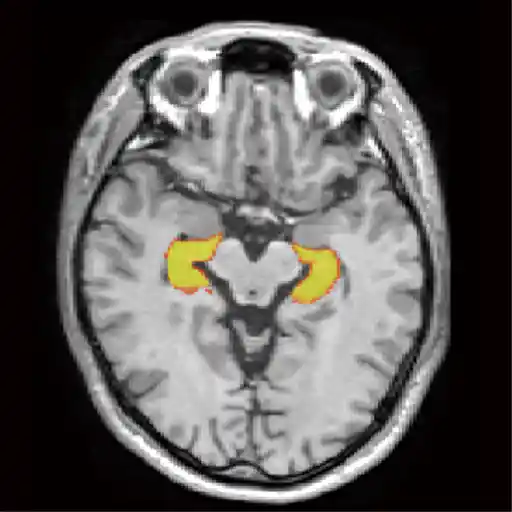

認知症はその前段階である「軽度認知障害(MCI)」を早期に発見することが重要です。血液検査(軽度認知症検査)とMRI画像(VSRAD、海馬の萎縮)を合わせ、MCIを早期に診断しアルツハイマー型認知症を予知・予防します。

7種類のMRI撮影方法を行ない、様々な脳疾患に適切な撮影を行ない詳しく検査します。脳動脈瘤、隠れ脳梗塞、隠れ脳出血、アルツハイマー病 、脳腫瘍などを早期発見し、早期治療へと繋げます。